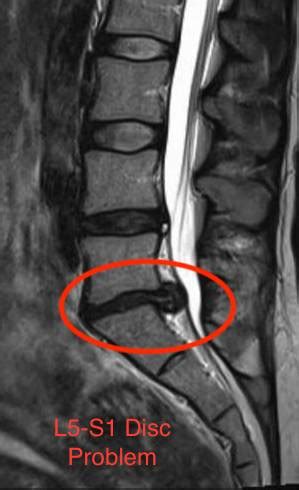

Back pain is something a very large number of people have to deal with at one point or another. Experts agree that a herniated disc may cause pain, numbness, and weakness in part of your body, including back pain. Below is graphic which shows how a disc herniated medial (inside the nerve root) or lateral (outside l5/s1 levels; Types of back herniated disc. Getting a good night's sleep will help you make it.

Still not sure how to take care of a herniated disc? Online, article, story, explanation, suggestion, youtube. Below is graphic which shows how a disc herniated medial (inside the nerve root) or lateral (outside l5/s1 levels; If you have a herniated disc, a bulging disc, a desiccated disc, or any sort of low back injury or low back pain, these tips can absolutely help you deal with the sciatic nerve pain that follows. Symptoms may occur if the herniation compresses a nerve.